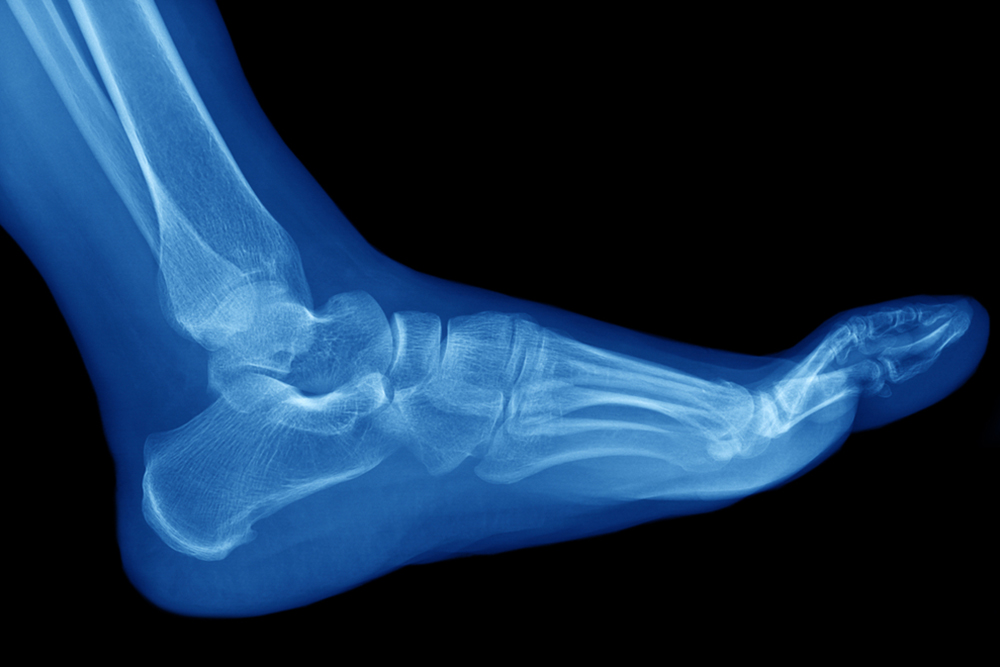

The Achilles tendon is a tendon that connects the lower leg muscles and calf to the heel of the foot. It is the strongest tendon in the human body and is essential for making movement possible. Because this tendon is such an integral part of the body, any injuries to it can create immense difficulties and should immediately be presented to a doctor.

Achilles tendon injuries are diagnosed by a thorough physical evaluation, which can include an MRI. Treatment involves rest, physical therapy, and in some cases, surgery. However, various preventative measures can be taken to avoid these injuries, such as: